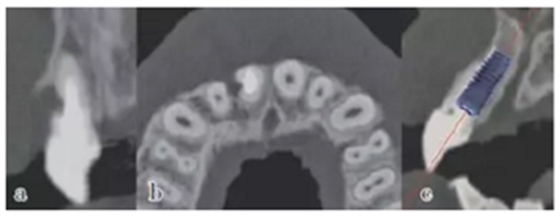

患牙21因根管治療超充,導(dǎo)致根尖周炎,唇側(cè)齲壞并出現(xiàn)瘺管。擬采用即刻種植修復(fù)。術(shù)前拍攝CBCT并做種植方案規(guī)劃,從方案上可知唇側(cè)及遠(yuǎn)中側(cè)骨缺損較為嚴(yán)重,需要同期進(jìn)行引導(dǎo)骨再生術(shù)(GBR)。

圖9 種植方案規(guī)劃:a.近遠(yuǎn)中方向的截面圖,唇側(cè)需要GBR;b.軸向截面圖;c. 模擬植入4.0×13 mm 的種植體